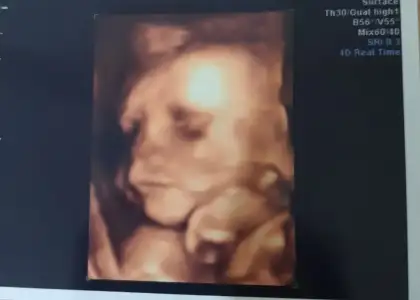

Slmlar herkese bizim bugun doktor ziyaret günümüzdu tam 26+0 810 grm 32 santimmisiz kafası sağ kaburgamın altindaymis ters duruyo dedi böbrek ağrın olursa panik yapma dedi bebis hep bi yerdeymis çünkü bu da resmimiz💕

• Screenshot_20220416-191852_Gallery.webp

Screenshot_20220416-191852_Gallery.webp

11 KB · Görüntüleme: 105